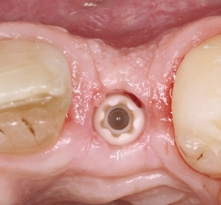

Der klinische Befund zeigte eine definitive Versorgung auf 12 und eine temporäre Versorgung auf 22. Dahingegen lag bei der Implantatversorgung in regio 22 der Verdacht auf eine partielle Fibro-Osseointegration vor (Abb. 1 und 2) [9,10].

Der chirurgische Eingriff wurde unter Lokalanästhesie mit palatinaler und labialer Infiltration durchgeführt. Zuerst erfolgte die Entfernung des Implantats. Für die Explantation wählten wir das aus unserer Sicht knochenschonendste Verfahren. Mithilfe einer Extraktionszange und mit entsprechend dosierter Kraft drehten wir das teilweise ankylotische Implantat in Achsrichtung aus, um auf jeden Fall die dünne labiale Knochenlamelle zu erhalten (Abb. 3). Dabei frakturierte der osseointegrierte Implantatapex tief im Implantatbett (Abb. 4). Um diesen zu entfernen, musste ein minimalinvasiver apikaler Zugang geschaffen werden. Nach einer krestalen Inzision mit mesialer Tunnelpräparation und distaler Entlastungsinzision sowie der Präparation eines Mukoperiostlappens zeigte sich ein ausgeprägter konkaver Alveolarknochen. Mit einem piezotechnisch unterstützten Chirurgieansatz fenestrierten wir die labiale Knochenlamelle (Abb. 5). Durch diesen minimalinvasiven Zugang lösten wir die ankylotische Verbindung und entfernten den apikalen Implantatrest. Bei dieser Methode der Implantatentfernung wird der periimplantäre krestale Knochen weitestgehend geschont.